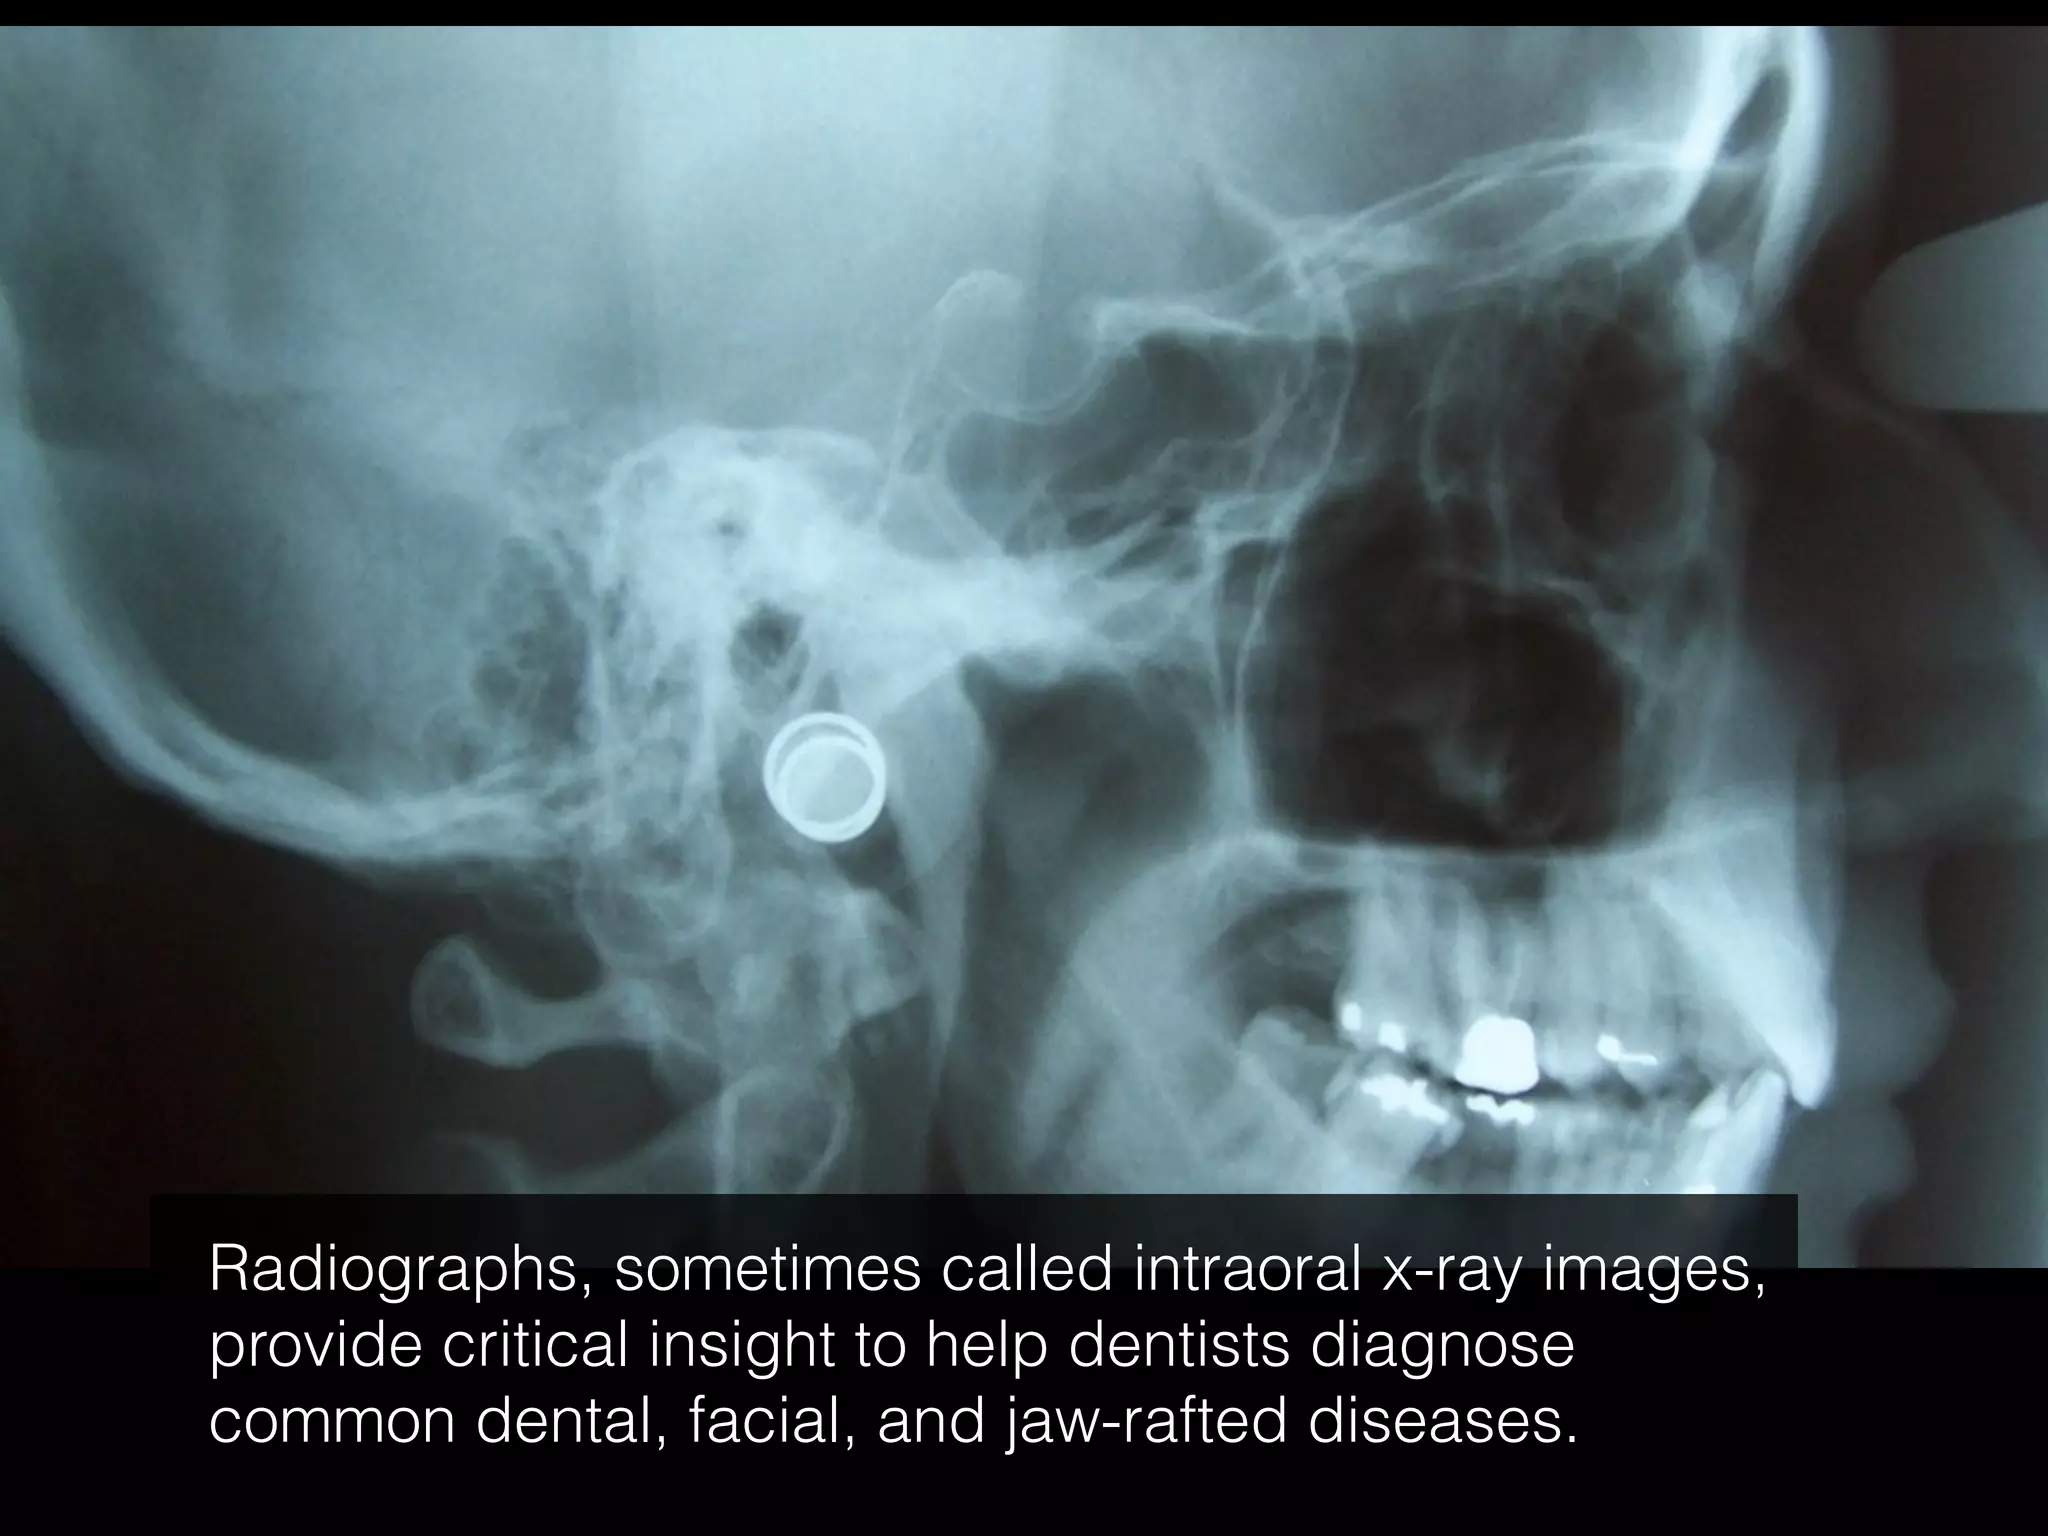

The document discusses the history and advancements in radiology, highlighting Wilhelm Conrad Röntgen's discovery of x-rays in 1895 and the subsequent Nobel Prize winners who utilized this technology. It also covers the evolution of radiology beyond x-rays to include ultrasound, magnetic fields, and radioactivity, as well as the critical role of barium in radiological practices. Additionally, it notes the potential risks of ionizing radiation on organic cells and DNA.